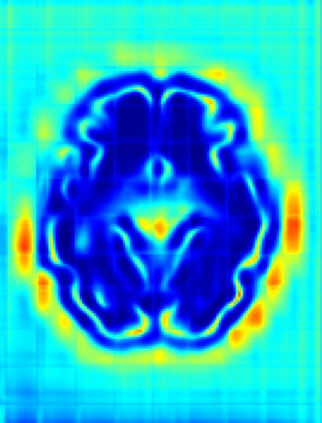

Fetal cortical plate segmentation is essential in quantitative analysis of fetal brain maturation and cortical folding. Manual segmentation of the cortical plate, or manual refinement of automatic segmentations is tedious and time-consuming. Automatic segmentation of the cortical plate, on the other hand, is challenged by the relatively low resolution of the reconstructed fetal brain MRI scans compared to the thin structure of the cortical plate, partial voluming, and the wide range of variations in the morphology of the cortical plate as the brain matures during gestation. To reduce the burden of manual refinement of segmentations, we have developed a new and powerful deep learning segmentation method. Our method exploits new deep attentive modules with mixed kernel convolutions within a fully convolutional neural network architecture that utilizes deep supervision and residual connections. We evaluated our method quantitatively based on several performance measures and expert evaluations. Results show that our method outperforms several state-of-the-art deep models for segmentation, as well as a state-of-the-art multi-atlas segmentation technique. We achieved average Dice similarity coefficient of 0.87, average Hausdorff distance of 0.96 mm, and average symmetric surface difference of 0.28 mm on reconstructed fetal brain MRI scans of fetuses scanned in the gestational age range of 16 to 39 weeks. With a computation time of less than 1 minute per fetal brain, our method can facilitate and accelerate large-scale studies on normal and altered fetal brain cortical maturation and folding.